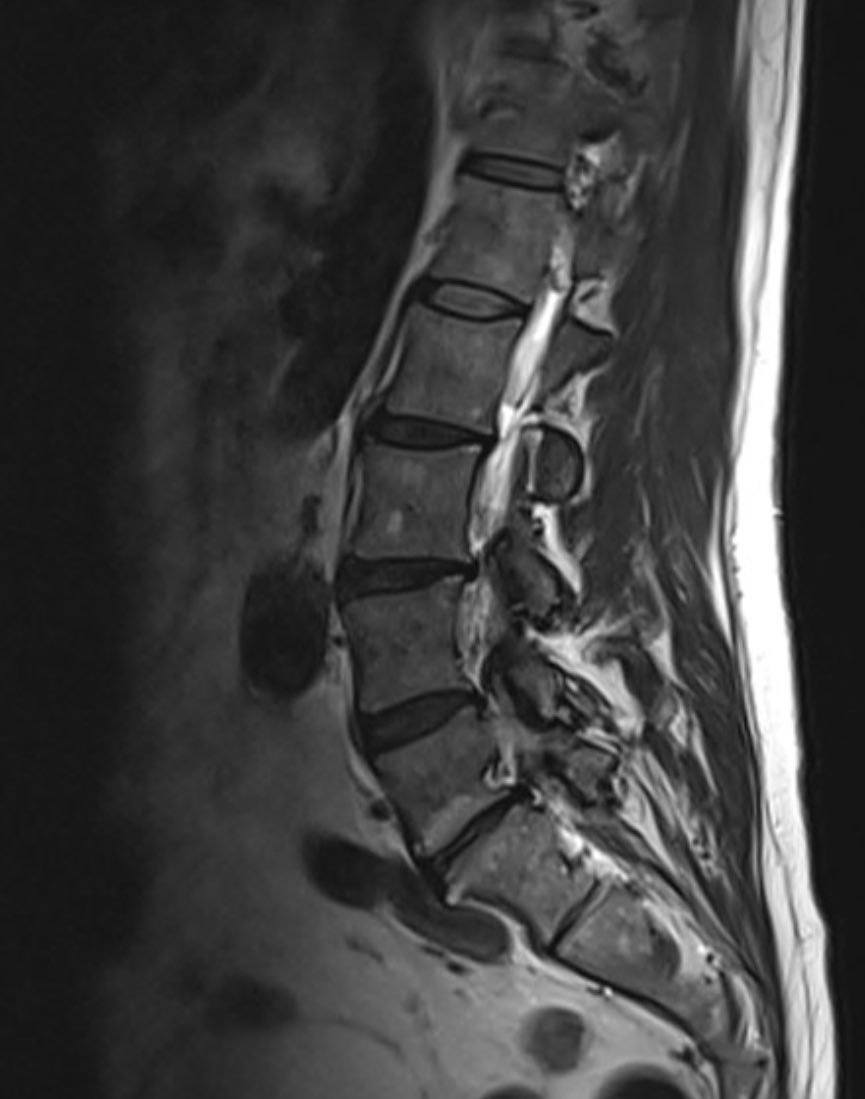

6. request mri LSp - spondylolisthesis L5/S1 and facet hypertrophy causing nerve root compression (bilateral!), associated disc Modic 1 changes